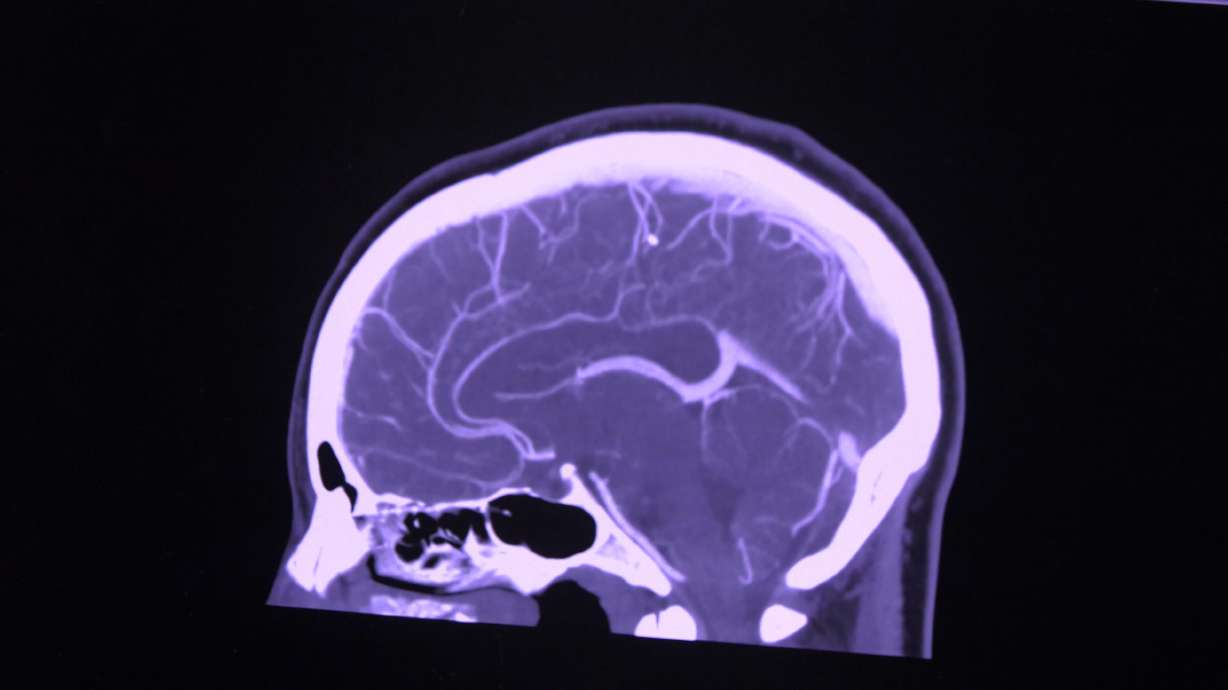

By the time they were at the hospital, K.C.'s left peripheral vision was gone, and he was having a hard time.

Shortly after receiving tissue plasminogen activator medication, also known as tPA, K.C. Seeley said he was able to move his arm again, and his vision got clearer — although it took months for his vision to return to where it is now with just a spot of blurriness.

Dr. Kathleen McKee, a neurologist at Intermountain Medical Center, said, "It really is a situation where seconds matter, and so having an algorithm where you can get the medicine in as quickly but safely as possible is really important."

McKee said now about 90% of eligible patients receive tPA, the clot-bursting medication, within an hour of being admitted to the hospital, leading to more brain cells saved and less risk of permanent disability.

"We are chasing perfection here. We were shaving five, 10, 15, 20 minutes off these times, but that's a lot of neurons. And so those 20 minutes matter quite a bit," she said.